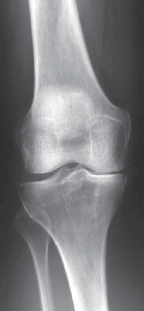

A library of advanced orthopedic surgical techniques, providing step-by-step guidance for complex musculoskeletal procedures.